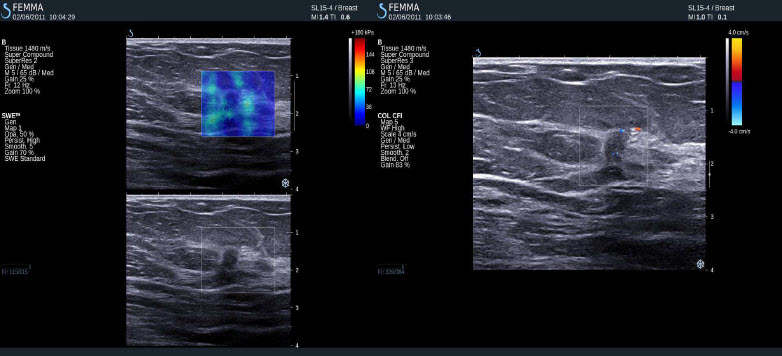

Negativní výsledky elastografie / histologicky potvrzená benignita

Duktální hyperplazie, sklerozující adenoza, mikrokalcifikace